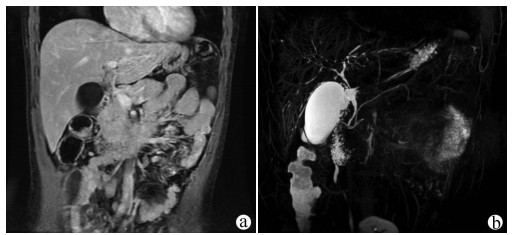

A case of splenic arteriovenous fistula with abdominal pain and gastrointestinal bleeding as the first symptoms

Yuanyuan CAI, Zhongwen WU, Juan LU

2021, 37(5): 1186-1188. DOI: 10.3969/j.issn.1001-5256.2021.05.043

Abstract(1061) HTML (301) PDF (2876KB)(57)

Abstract: